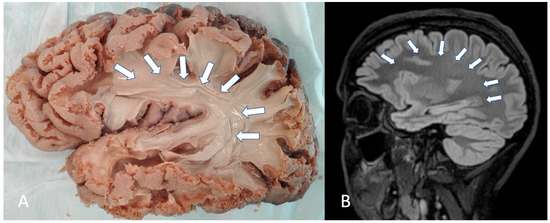

- Altieri, R.; Melcarne, A.; Junemann, C.; Zeppa, P.; Zenga, F.; Garbossa, D.; Certo, F.; Barbagallo, G. Inferior Fronto-Occipital Fascicle Anatomy in Brain Tumor Surgeries: From Anatomy Lab to Surgical Theater. J. Clin. Neurosci. 2019, 68, 290–294. [Google Scholar] [CrossRef]

- Sarubbo, S.; De Benedictis, A.; Merler, S.; Mandonnet, E.; Barbareschi, M.; Dallabona, M.; Chioffi, F.; Duffau, H. Structural and Functional Integration between Dorsal and Ventral Language Streams as Revealed by Blunt Dissection and Direct Electrical Stimulation. Human. Brain Mapp. 2016, 37, 3858–3872. [Google Scholar] [CrossRef]